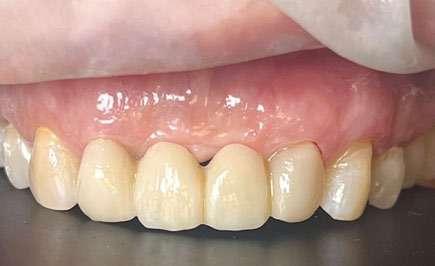

Figuras 3-6. Imágenes de un caso de prótesis atornillada en molar unitario inferior. Vemos el estado de los tejidos blandos gingivales tras la segunda fase y colocación del transepitelial unitario y la radiografía. En las imágenes inferiores (5 y 6) observamos el caso a los 4 años y 10 años de seguimiento, con estabilidad completa de los tejidos óseos peri-implantarios.

Figuras 7-10. En las dos imágenes superiores (7 y 8) observamos la realización de la prótesis cementada mediante un bioplilar fresado a la altura gingival con la radiografía antes del cementado de la corona. En las imágenes inferiores (9 y 10) vemos la prótesis a los 7 años de seguimiento y a los 9 años transformada en una prótesis atornillada al perderse la pieza anterior al implante y realizarse un puente con el nuevo implante. En este caso, el nivel óseo permanece estable con el paso del tiempo.